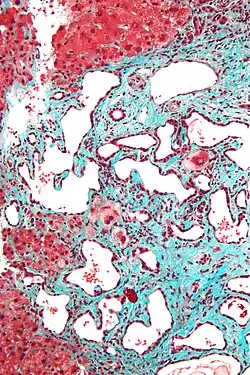

Histopathology of a bile duct hamartoma, high magnification, H&E stain. It shows typical features of bile duct hamartoma: Small to medium sized, irregularly shaped bile ducts lined by bland cuboidal epithelium (may also be flattened). Prominent intervening collagenous stroma. Bile ducts containing eosinophilic debris (may also contain inspissated bile) -

Low magnification micrograph of a bile duct hamartoma. Trichrome stain. -